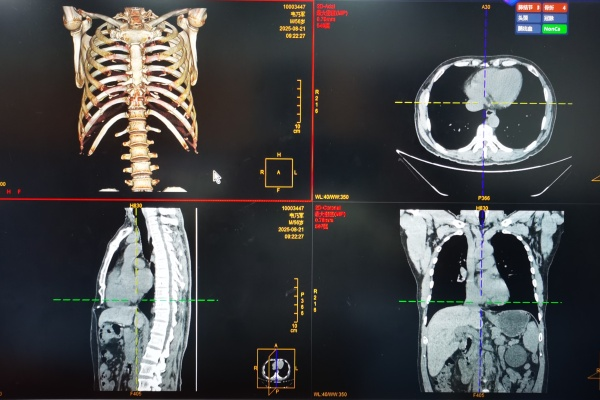

CT(电脑断层扫描)与MRI(核磁共振扫描)也不示弱,纷纷争相数码化改造,它们提供的是三维立体的图像,医生可以360度看人体内部,医院影像科的医生们围着电脑,面对高清的影像讨论诊断,诊断率大大提升。

不仅如此,数字化的另外一个优势在于影像的可传输,医院内部的PACS(Picture Archive System)充当了“快递员”的角色,将影像从检查室及时无误的传输到医生的电脑中,无论是在门诊、病房,还是检查室、办公室,都能随时获取影像。